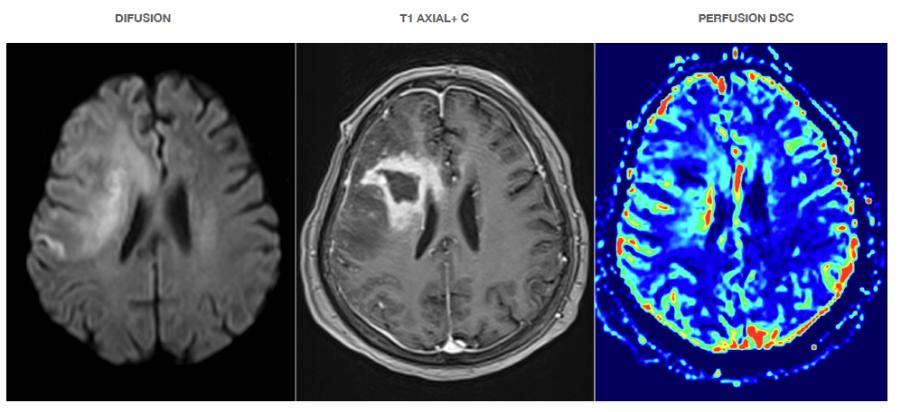

Púrpura Trombocitopenica Inmune como manifestación inicial de lesión tumoral cerebral Immune Thrombocytopenic Purpura as initial manifestation of brain tumor

Nicolas Gabriel Rojas, Stambuk Ivanova Saavedra Tapia .........................................................................39-47